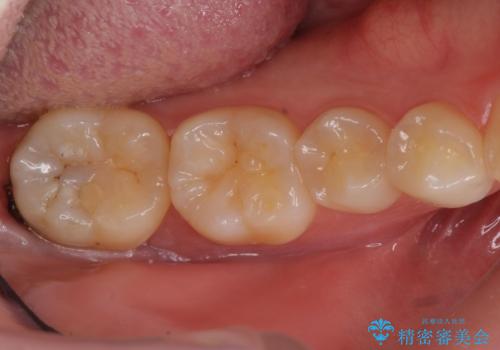

虫歯治療後、精度の良いゴールドアンレーへ

- 検査の結果虫歯が見つかった患者様です。

親知らずを抜歯してから虫歯を除去した後、ゴールドの詰め物で修復します。

比較的大きな虫歯でしたがゴールドでの修復にすることで歯の削る量を抑え、精度の高い治療を行うことができました。

親知らずの問題も同時に解決することで今後の虫歯リスクを抑えています。